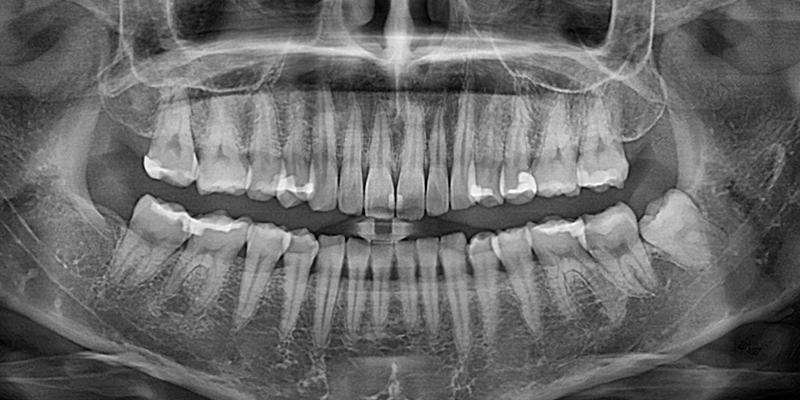

X線の前に

手術前のX線撮影です。

X線撮影で親知らずの位置を正確に把握します。